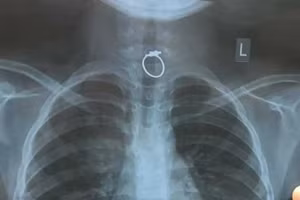

Ngậm chiếc nhẫn chơi trong miệng, bé gái 10 tuổi nuốt luôn vào bụng 16/02/2021 11:07 GD&TĐ - Bệnh viện Nhi Đồng TPHCM cho biết, các bác sĩ của bệnh viện vừa cấp cứu thành công cho bé gái 10 tuổi nuốt phải chiếc nhẫn khi đang ngậm chơi trong miệng.